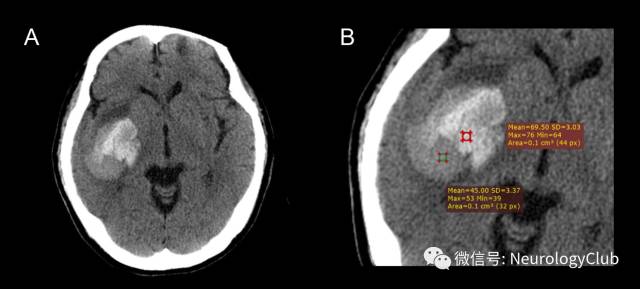

黑洞征

2016年,李琦等在ICH患者CT平扫影像中发现黑洞征,将其定义为血肿内黑洞(低密度区)被相邻高密度血肿完全包裹的现象,且需满足:(1)形状各异(可为近圆形或杆状),但与邻近脑组织不相连;(2)有明显的边界;(3)血肿内两密度区的CT值至少相差28HU。黑洞征预测ICH患者早期血肿扩大的敏感性、特异性、阳性预测值及阴性预测值分别为31.9%、94.1%、73.3%及73.2%。血肿的异质性可能反映不同时期的出血,新鲜出血在CT图像中表现为低密度;血液凝固后,血清从中分离,在CT中则表现为高密度。黑洞征的出现表明异质血肿内存在不同时期的出血,因此可作为ICH患者血肿扩大的预测因素。

(图5:脑出血黑洞征